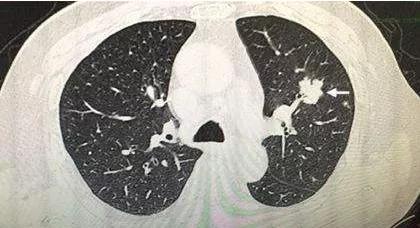

入院后,李女士接受了PET-CT等一系列详细的检查。结果显示,她的右肺上叶结节首先考虑为肺癌,并且已经出现了双肺多发转移瘤、全身多发骨转移瘤、右侧大脑顶叶转移瘤以及腹膜转移瘤。肿瘤活性值最高达到了48,提示肿瘤处于高活跃状态。

面对这样的诊断结果,李女士和家人都陷入了深深的震惊与绝望。为了明确诊断,李女士接受了肺结节及胸膜结节活检。术后病理报告显示,她患的是肺腺癌。基因检测也进一步确认了这一结论。